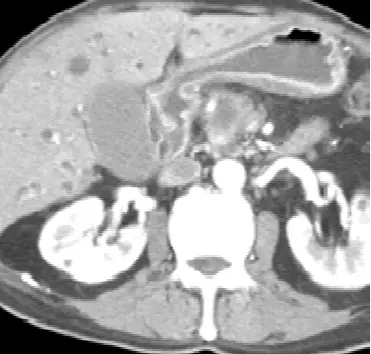

本題考核胰臟頭癌(pancreatic head cancer)的典型臨床表現與影像診斷。老年男性出現疲倦、食慾減退、皮膚黃疸(obstructive jaundice),合併 CA 19-9 升高,搭配 CT 及膽道攝影影像,是胰臟頭癌的典型呈現。

影像二(腹部 CT 橫切面,胰臟層面): 在胰臟頭部區域可見一低密度(hypodense)腫塊,腫塊邊界不清,周圍正常胰臟實質受壓。總膽管(common bile duct, CBD)可見擴張。此種「乏血管性(hypovascular)」低密度腫塊在動脈期 CT 上相對於周圍正常胰臟實質呈低密度,是胰臟腺癌(pancreatic adenocarcinoma)的典型影像特徵。